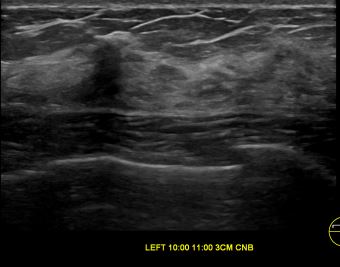

상기환자는 외부검사 이상소견으로 내원하신 50대초반 여성분으로 의심스러운 좌측혹 조직검사 시행해 유방암으로 진단되었습니다